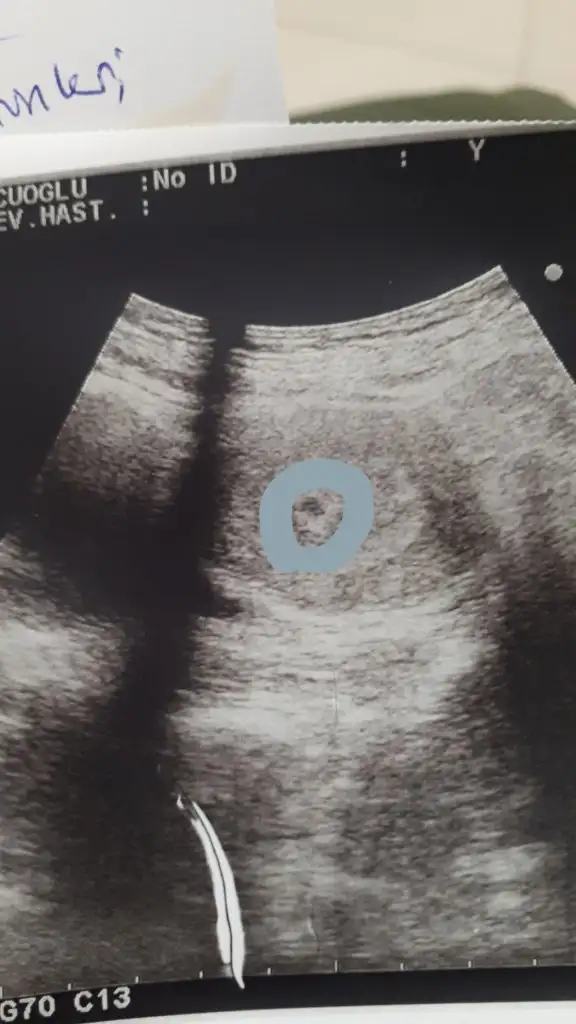

Canim benim beta pazartesi 8179 du bugun dr gittim bebisi gorduk. Dun lejem gelmisti biraz. Bebegin altinda kan birikintisi var resimdede gorunuyor. Ama bebek iyi kesesi duzenli dedi. Kani vucut emebilirmis yada aticak. Buyuzden istirahat ve progestan verdi. Benim ilk bebegimde bu sekilde olmustu 3 aya yakin kananam olmusdu ama saglikla dogdu. Bata gore 6 haftanin icindeyim ama dr 5. Hafta boyutunda dedi. Normalmis.Kızlar 6-7 haftalık olanlarda ultrason görüntüsü varsa rica etsem atabilir mi benim birşey belli olmuyorda merak ettim

Kızlar 6-7 haftalık olanlarda ultrason görüntüsü varsa rica etsem atabilir mi benim birşey belli olmuyorda merak ettim